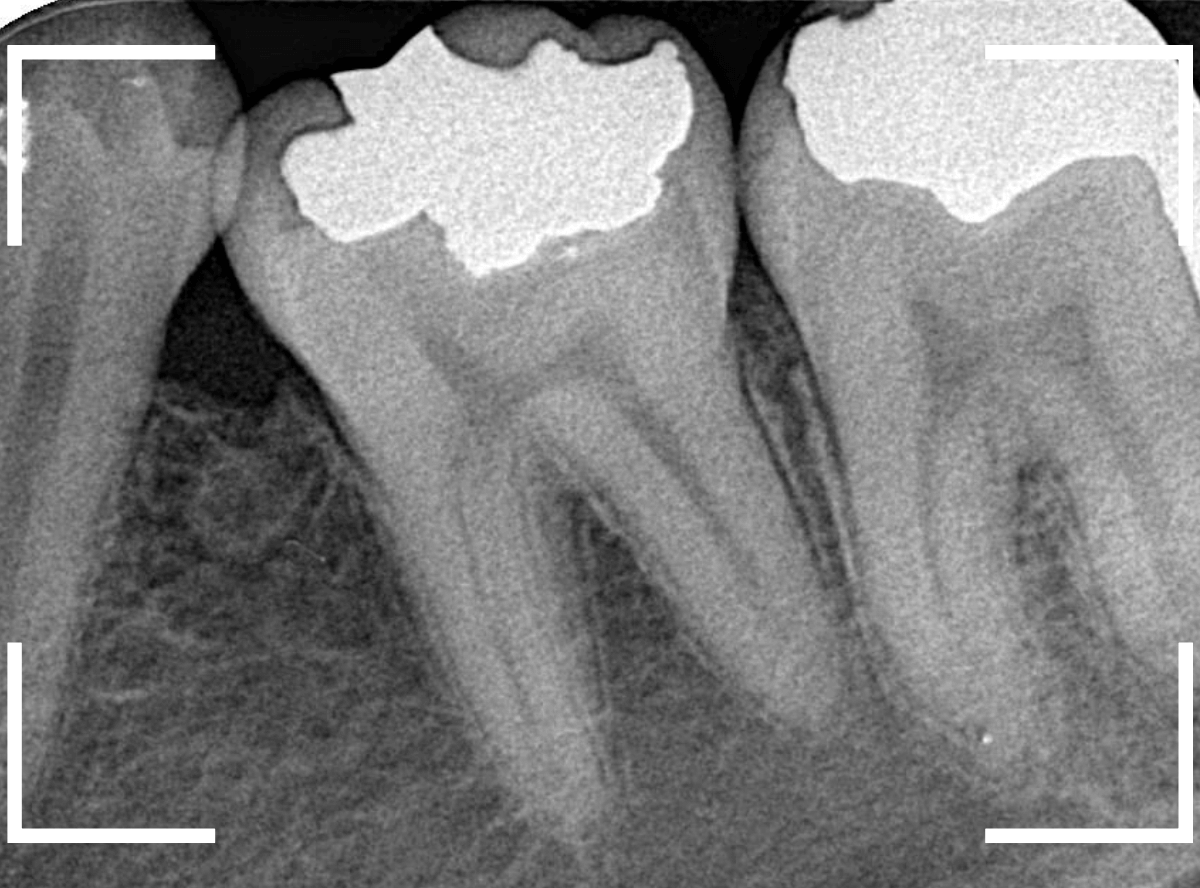

Case.17 レントゲンにはっきり写らないレジンの中の虫歯を削って調べる2

青いラインが歯の神経です。

以前の虫歯が深めだったようで、レジンが深めにつめてあるのがわかります。

その下がうっすらと虫歯っぽい影になっています(赤いライン)。

虫歯になっているか微妙なラインですが、レジンも劣化していますので、患者さんにご説明して治療することになりました。

さて、レントゲン写真で確認すると、上の写真の歯のレジンをつめてある下が少し虫歯っぽい写り方をしています。

レントゲン写真で確認します。

あまりはっきりしませんが、レジンの下で虫歯がありそうな感じです。

レジンの下の赤い色の線が虫歯であろうと思われる部分です。

痛みのある歯については、なんとも微妙な写り方に見え、虫歯だと断言し難い状況でした。

このような場合は、症状とレントゲン写真などから推察していくのですが、痛みは噛んだ時のみで、虫歯特有のしみるなどの症状がないため、そこからも判断しづらい状況でした。

特に虫歯はなさそうに見えますが、側面の虫歯なので、虫歯が中で広がっている可能性も頭をよぎります。

虫歯があるのかはっきりしない写り方です。

何はともあれ、レントゲン写真で確認します。

黒い点の前後がボヤっと黒っぽく写ります。

何かありそうにも何もなさそうにも見える、あいまいな写り方です。

さすがにレントゲン写真でも虫歯がありそうな事は確認できますが、実際にどうなってるのかはあまりはっきりわかりません。

レントゲン写真では、あまり大きな虫歯のようには見えません。

治療前にレントゲン写真で虫歯の大きさを確認するつもりが・・・あまりはっきり写ってきません。

レントゲン写真で確認しますが、ここでは特に問題はなさそうに見えます。

うーん、この写真からだと、どの程度の虫歯かちょっとわかりづらい感じです。

右側の部分の虫歯は少し進行してそうですけどね。

レントゲンでは、黄色い丸の部分は虫歯ではなさそうに見えます。

逆に反対側のオレンジ色の丸の部分にレジンがつまっていて、中で虫歯になっていそうなのはわかります。

レントゲン写真で確認しますが、虫歯らしき写り方はしていません、浅い虫歯なのでしょうか。

まずはレントゲン写真で確認です。

う~ん、意外と虫歯は大したことないのでしょうか。

あまりそれらしい写り方はしていません。

レントゲン撮影をして、確認しました。

・・・が、レントゲン上では、虫歯ははっきりわかりません。

レントゲンで確認します。

虫歯があると思われる部分がレジンで隠れてしまって、よくわからないです。

むしろ隣の奥の歯の方が虫歯っぽく見えます。